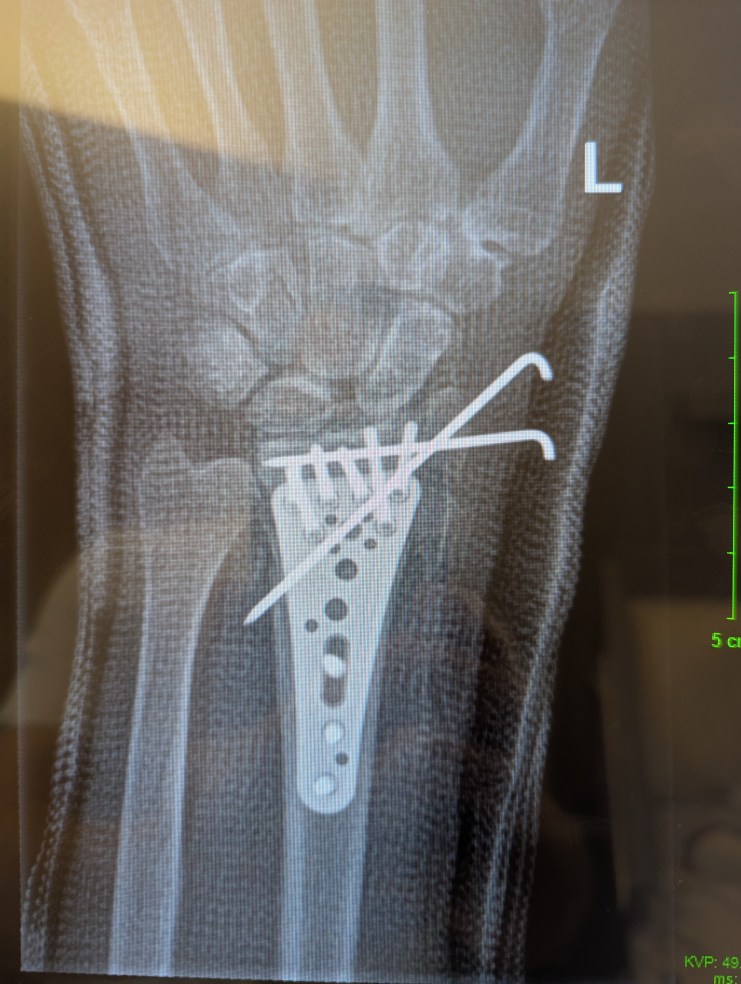

Binnen Sekunden sind die Bohrdrähte herausgezogen. Völlig schmerzlos. Ein wenig Blut ist geflossen, aber kaum der Rede wert. Ich bin erleichtert. Der nächste Schritt ist eine Röntgenaufnahme und wir werden besprechen, wie die Therapie aussehen wird. Sie besteht auf eine stationäre Behandlung. Zweimal wöchentlich im Krankenhaus. Einen Monat lang. Dann sehen wir weiter.